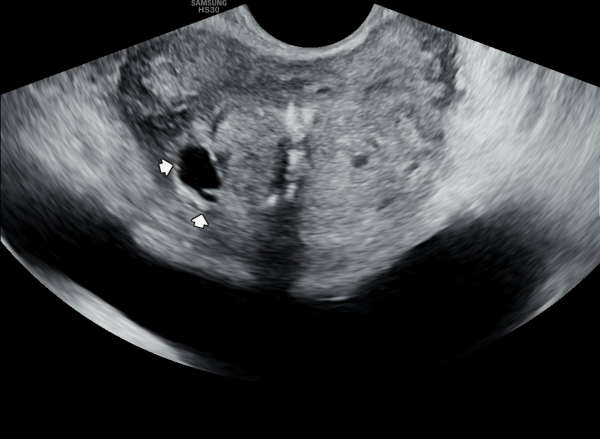

10년전부터 배뇨장애와 빈뇨로 비뇨기과에서 약을 복용중 2년전부터 급박뇨와 요실금이 심해져 투약을 했으나 증상의 호전이 없다고 내원당일 검사한 경직장 전립선 초음파 검사상 전립선 비대와 전립선의 낭종과

사정관주위의 결석이 관찰되는 경직장 전립선 초음파 사진입니다.

This is a transrectal prostate ultrasound image taken on the day of the visit. The patient had been taking medication for urinary difficulties and frequent urination for over 10 years at a urology clinic. However, since two years ago, symptoms of urgency and urinary incontinence worsened despite continued medication. The ultrasound shows prostate enlargement, cysts within the prostate, and calcifications around the ejaculatory ducts.